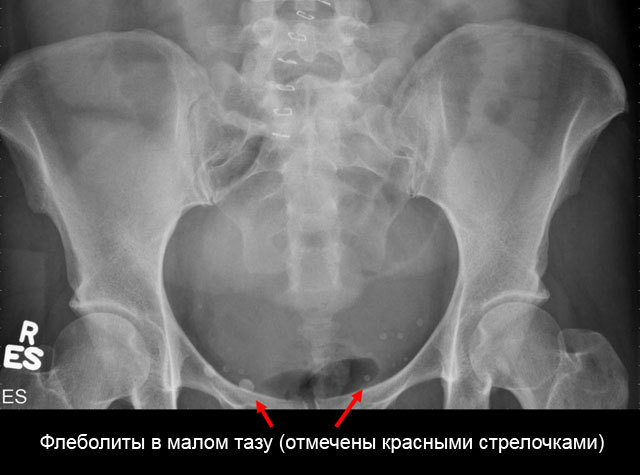

Флеболит это небольшие частички закальцинированных тромбов, которые образовываются в венах. На рентгеновских снимках проявляются в виде белых пятен.

- Рентген. Снимок позволяет определить точную локализацию камней. Они имеют овальную форму, характерную концентрацию.

Кальциевые камни органов или вен малого таза наиболее часто обнаруживаются случайно на рентген-снимках в виде мелких камнеобразных уплотнений. Для определения точной локализации, а также размера образований проводят магнитно-резонансную или компьютерную томографию, позволяющую оценить их особенности в различных проекциях.

По данным некоторых авторов, на четверти всех рентгенограмм малого таза, сделанных по разным причинам, обнаруживаются тени флеболитов.

- Рентгенография определяет флеболиты в проекции малого таза в виде округлых теней с множеством слоев. Важным диагностическим признаком является наличие радиопрозрачного центра (симптом «хвоста кометы»).

- Рентгенография малого таза. На обзорных снимках рентгеноконтрастные флеболиты видны как овальные структуры с концентрическими кольцами («расслоениями»). Важными диагностическими признаками тазовых камней принято считать наличие радиопрозрачного центра, симптом «хвоста кометы».